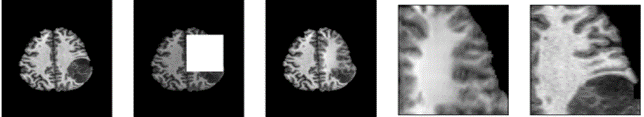

As shown in figure 2, one can see how the problem definition changed according to the amount of data masked. For smaller window sizes, the inpainting network is only required to reconstruct a handful of pixels. However, with larger masks the network is required to reconstruct texture and structure. Additionally, due to adversarial training, the network produces reconstructions without blur.

Figure 5 illustrates snapshots of the sliding window process. The inpainting network restores the masked region to what a normal brain would look like in that area. The inpainting network is naive and does not reconstruct the tumour when partially covered, due to computing L1 loss globally rather than just on the local masked region.